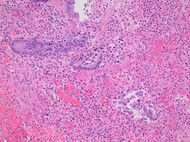

Even for clinically certain appendicitis, routine histopathology examination of appendectomy specimens is of value for identifying unsuspected pathologies requiring further postoperative management.[69] Notably, appendix cancer is found incidentally in about 1% of appendectomy specimens.[70]

Pathology diagnosis of appendicitis can be made by detecting a neutrophilic infiltrate of the muscularis propria.

Periappendicitis (inflammation of tissues around the appendix) is often found in conjunction with other abdominal pathology.[71]

Micrograph of appendicitis and periappendicitis. H&E stain

Micrograph of appendicitis showing neutrophils in the muscularis propria. H&E stain

Acute suppurative appendicitis with perforation (at right). H&E stain